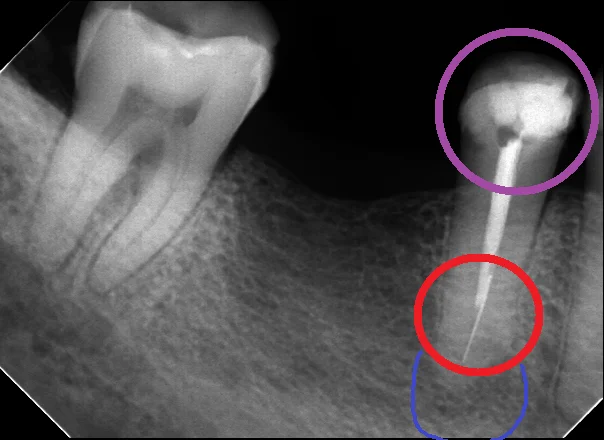

中心結節破折が原因で起こった神経の壊死を放置して、外部吸収が起こったケース

中心結節破折が原因で起こった神経の壊死を放置して、外部吸収が起こったケース